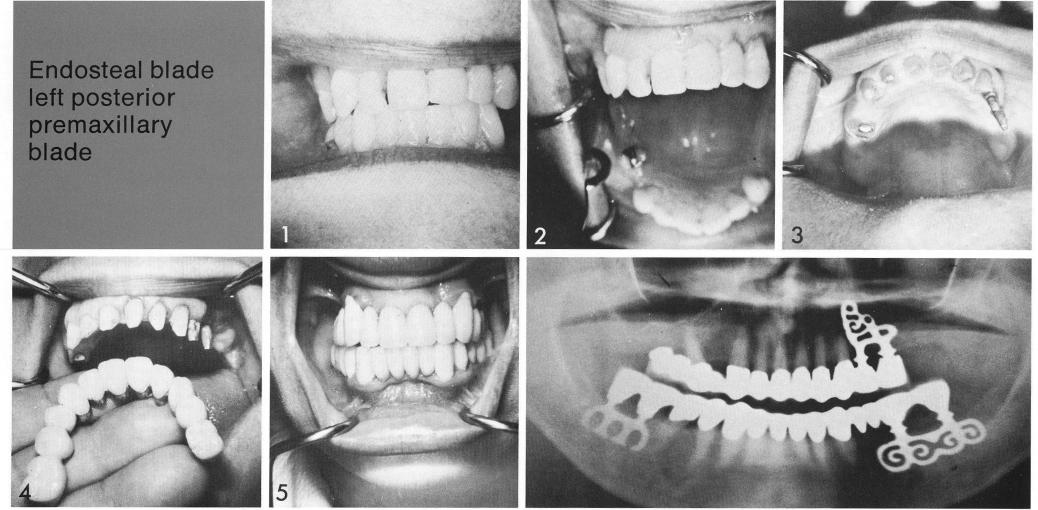

Endosteal blade

left posterior premaxillary blade

The patient was bilaterally, posteriorly edentulous, with very unattractive anterior teeth (1,2). A double-posted, sinus-circumventing bladevent was inserted on one side of the arch (3) to anchor a fixed palateless restoration that extended only through the first molar (4). Unopposed, more posterior crowns were unnecessary.